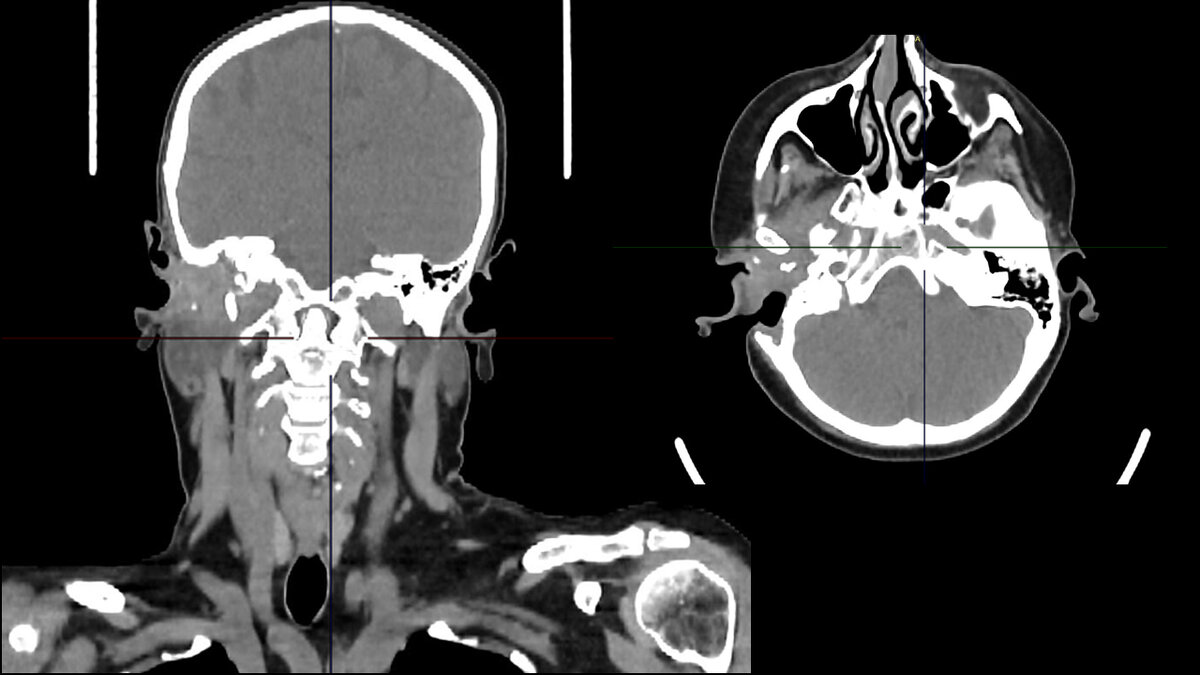

Пациентка 54 лет обратилась к ЛОР-врачам с жалобами на боль в правом ухе. Предварительный диагноз отит. Специалисты назначали консервативное лечение и противовоспалительную антибактериальную терапию, которые не принесли результата. При последующем осмотре слухового прохода специалисты заподозрили опухолевый процесс и провели биопсию. Однако результат не подтвердил наличие злокачественного новообразования. Пациентку оставили под динамическим наблюдением.

«Спустя 3 месяца с момента первичного обращения пациентка была экстренно госпитализирована в ГКБ им. М.Е. Жадкевича, где ей была выполнена профилактическая операция на правом ухе и взят повторный биоптат, - говорит заведующий отделением хирургии опухолей головы и шеи, д.м.н., врач-онколог, хирург Онкологического центра №1 ГКБ им. С.С. Юдина Сергей Анатольевич Кравцов. – Пересмотр биопсийного материала подтвердил злокачественный процесс редкой локализации, относительно других злокачественных новообразований кожи. Именно поэтому лор-врачам было сложно установить онкологический диагноз».

Пациентке была назначена консультация со специалистами Онкологического центра №1 ГКБ им. С.С. Юдина для определения дальнейшей тактики лечения. Для выполнения хирургического вмешательства было принято решение о создании мультидисплинарной команды специалистов, с участием врачей-оториноларингологов из НКИО им. Л.И. Свержевского, под руководством Гарова Евгения Вениаминовича, д.м.н., руководителя отдела микрохирургии уха и врачей-онкологов Онкологического центра №1 ГКБ им. С.С. Юдина, под руководством Кравцова Сергея Анатольевича, д.м.н. заведующего отделением хирургии опухолей головы и шеи, врача-онколога, хирурга.

8 февраля, 2024 года мультидисциплинарная команда специалистов Департамента здравоохранения Москвы выполнила пациентке хирургическое вмешательство в объеме паротидэктомии с невролизом лицевого нерва справа, лимфаденэтомии шейной расширенной справа, а также петрозэктомию с резекцией мягких тканей околоушной области, ушной раковины, слухового прохода с пластикой пекторальным лоскутом. Операция длилась около 6 часов.

«В ходе операции мы удалили околоушную слюнную железу, инфильтрованную опухолью, под контролем специального нейромонитора, который позволял нам отслеживать сохранность лицевого нерва, - поясняет доктор Кравцов. – Следующим этапом операции стало удаление фрагмента височной кости и формирование пекторального лоскута из мышцы передней грудной стенки для закрытия дефекта у основания черепа».